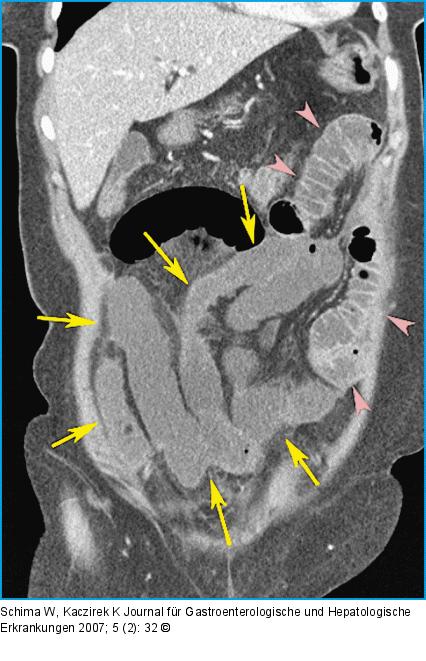

Abbildung 1C: CT-Rekonstruktion in koronaler Ebene Die CT-Rekonstruktion in koronaler Ebene zeigt gut die nekrotischen, dilatierten Ileumschlingen im rechten Mittel- und Unterbauch, welche kein Kontrastmittelenhancement aufweisen (Pfeile). Die Jejunumschlingen im linken Oberbauch sind normal (Pfeilspitzen). |

Die CT-Rekonstruktion in koronaler Ebene zeigt gut die nekrotischen, dilatierten Ileumschlingen im rechten Mittel- und Unterbauch, welche kein Kontrastmittelenhancement aufweisen (Pfeile). Die Jejunumschlingen im linken Oberbauch sind normal (Pfeilspitzen). |